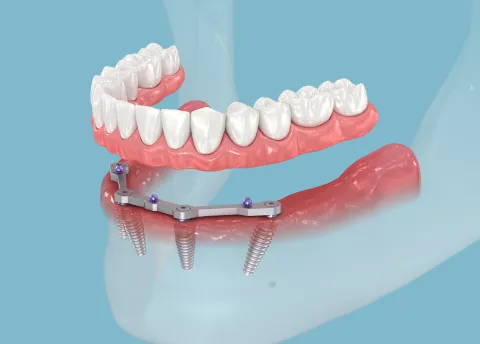

Welkom bij Sinident, uw tandartspraktijk in Sint-Niklaas, onder leiding van Lut Geers, gespecialiseerd in parodontologie en implantologie. Wij bieden volledige tandheelkundige zorg, van algemene tandheelkunde tot esthetiek, implantaten en chirurgie.

Specialisaties